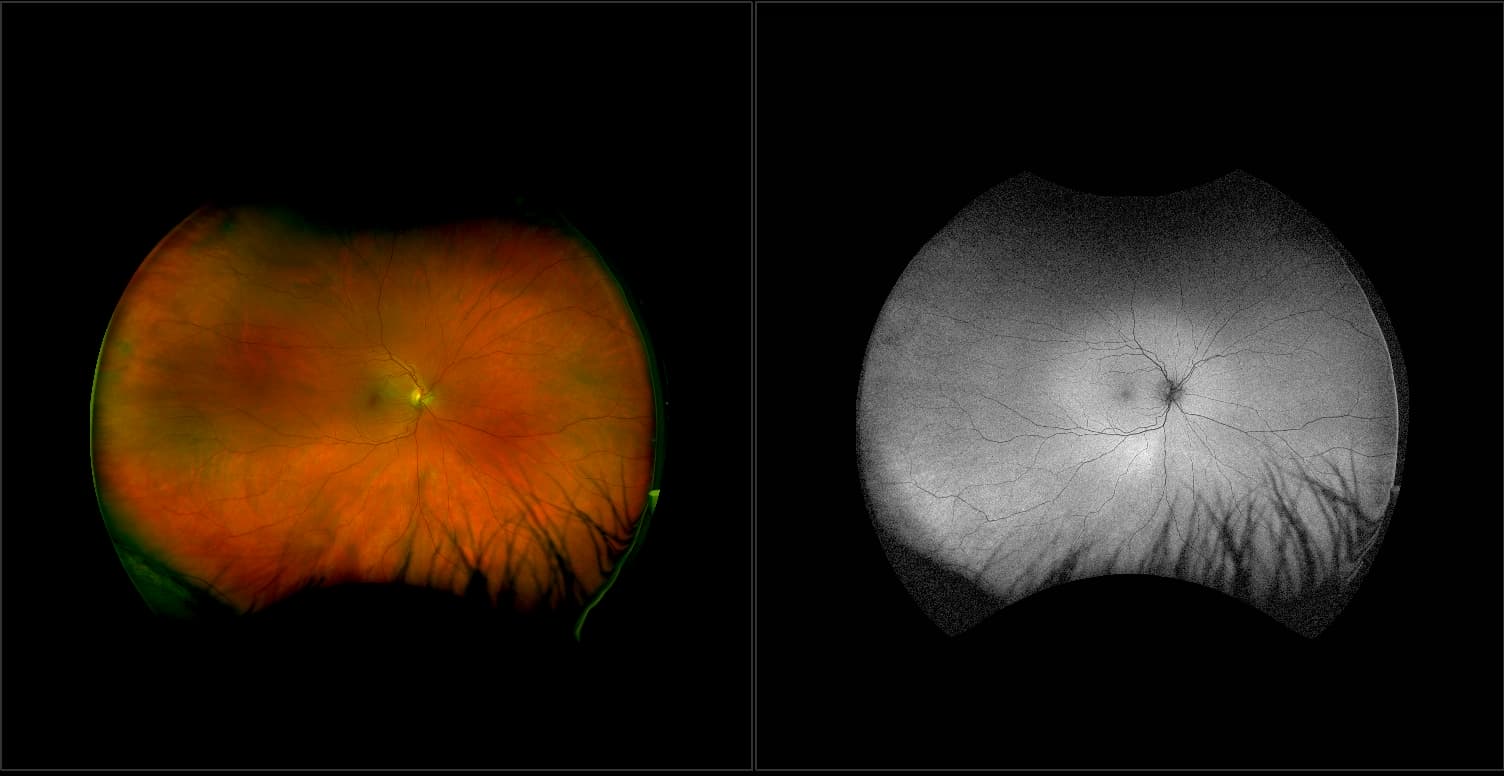

California - Choroidal Nevus, RG, AF

A choroidal nevus is simply an accumulation of melanocytes in the choroid. They are a space occupying mass or a benign melanoma. Choroidal nevi are slate gray in color, have indistinct margins, and may be slightly elevated (1-2 diopters). Since they are in the choroid, they are usually only seen in the red separation and not the green. The green separation may show the RPE degeneration associated with nevi which is seen as pigment mottling and drusen.